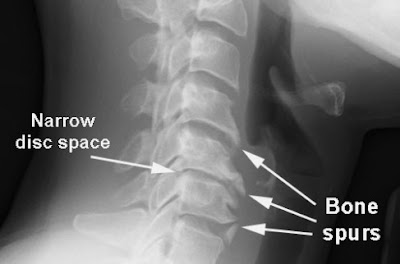

The pain sometimes spreads to his right shoulder and he feels tingling sensation in his right arm and hand. A Neck X ray was ordered and showed features of Cervical spondylosis:

- With gradual wear and tear , extra amount of bone is produced to strength the spine which leads to formation of bone spurs. These spurs can sometimes pinch the spinal cord and nerve roots.

- Neck X ray can show abnormalities like bone spurs.